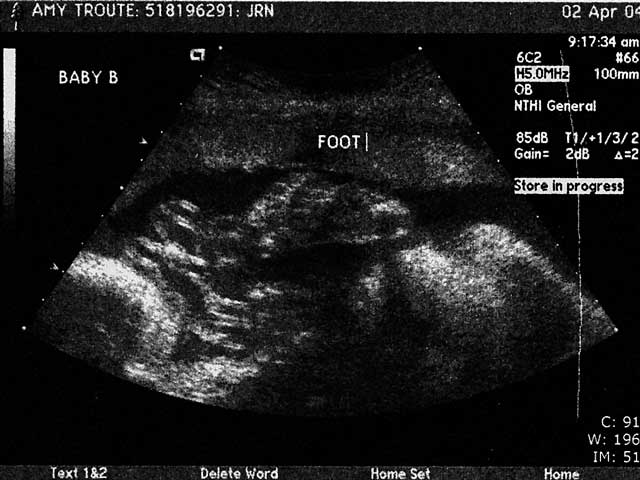

At one point we were able to get face-to-face with Baby B... It was yawning and touching its face cute little lips and nose and chin... I got all teary, Reese grabbed my hand what a moment!! Baby A was facing my back so we didnt get to see its face bummer! Stubborn little thing! Maybe well see its face at next months ultrasound were supposed to have one each month that remains... Yay!